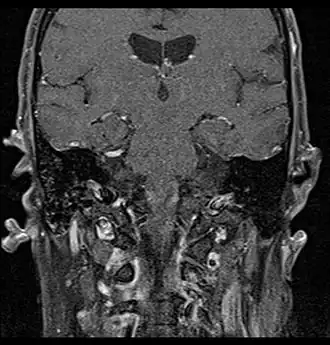

Primary treatment for this cancer, regardless of body site, is surgical removal with clean margins. This surgery can prove challenging in the head and neck region due to this tumor's tendency to show a perineural discontinuous growth, meaning that it follows nerves and different "nests" of the tumor can exist without a connection to the original tumor. Therefore, MRI-images should be analysed following nerve tracts up to the brainstem. Adjuvant or palliative radiotherapy is commonly given following surgery. For advanced major and minor salivary gland tumors that are inoperable, recurrent, or exhibit gross residual disease after surgery, fast neutron therapy is widely regarded as the most effective form of treatment.[13][14][15][16] Chemotherapy is used for metastatic disease. Chemotherapy is considered on a case-by-case basis, as data on the positive effects of chemotherapy are limited. Clinical studies are ongoing, however.